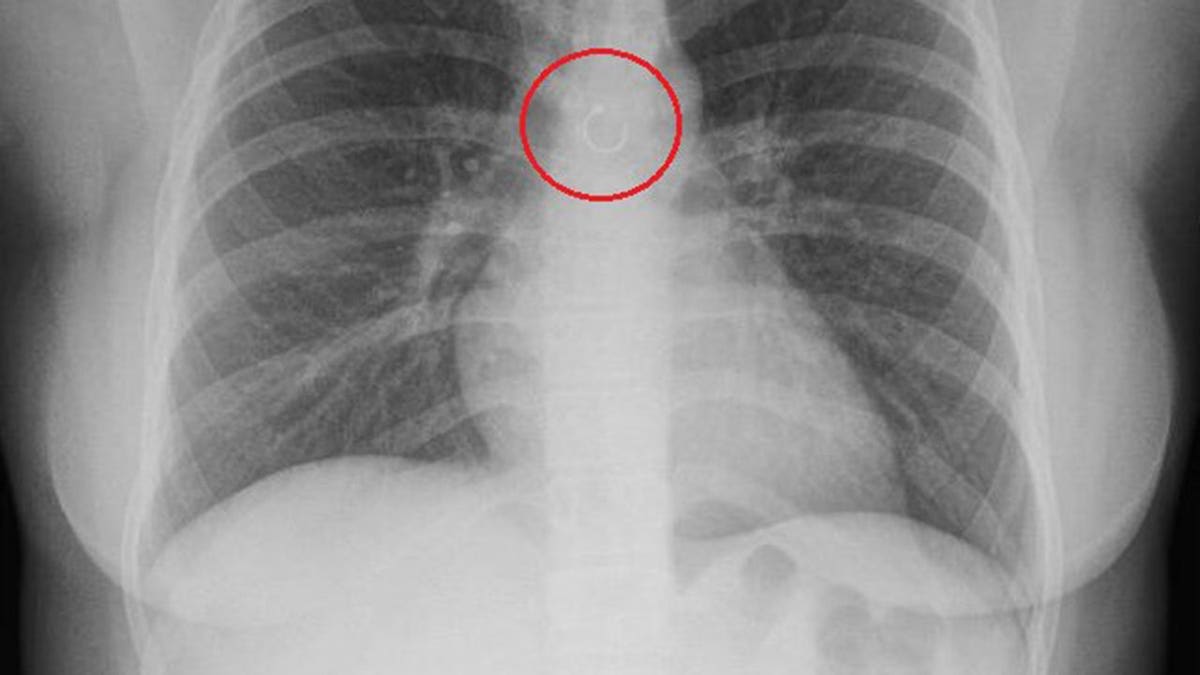

Monica Deyanira Cabrera Barajas thought the cough that wouldn't quit was just Mexico's changing weather getting to her. Instead, doctors found her missing nose ring lodged deep in her lung, sitting just half a millimeter from her aorta.

What doctors expected to be a simple 20-minute removal turned into an hour and 20 minutes of unsuccessful attempts. The metal ball had already started attaching to her internal tissue and sat dangerously close to her body's main artery.

If the ring had punctured her lung or aorta before discovery, doctors said she likely would have died from a collapsed lung or internal bleeding. The second surgery successfully removed the wayward jewelry.